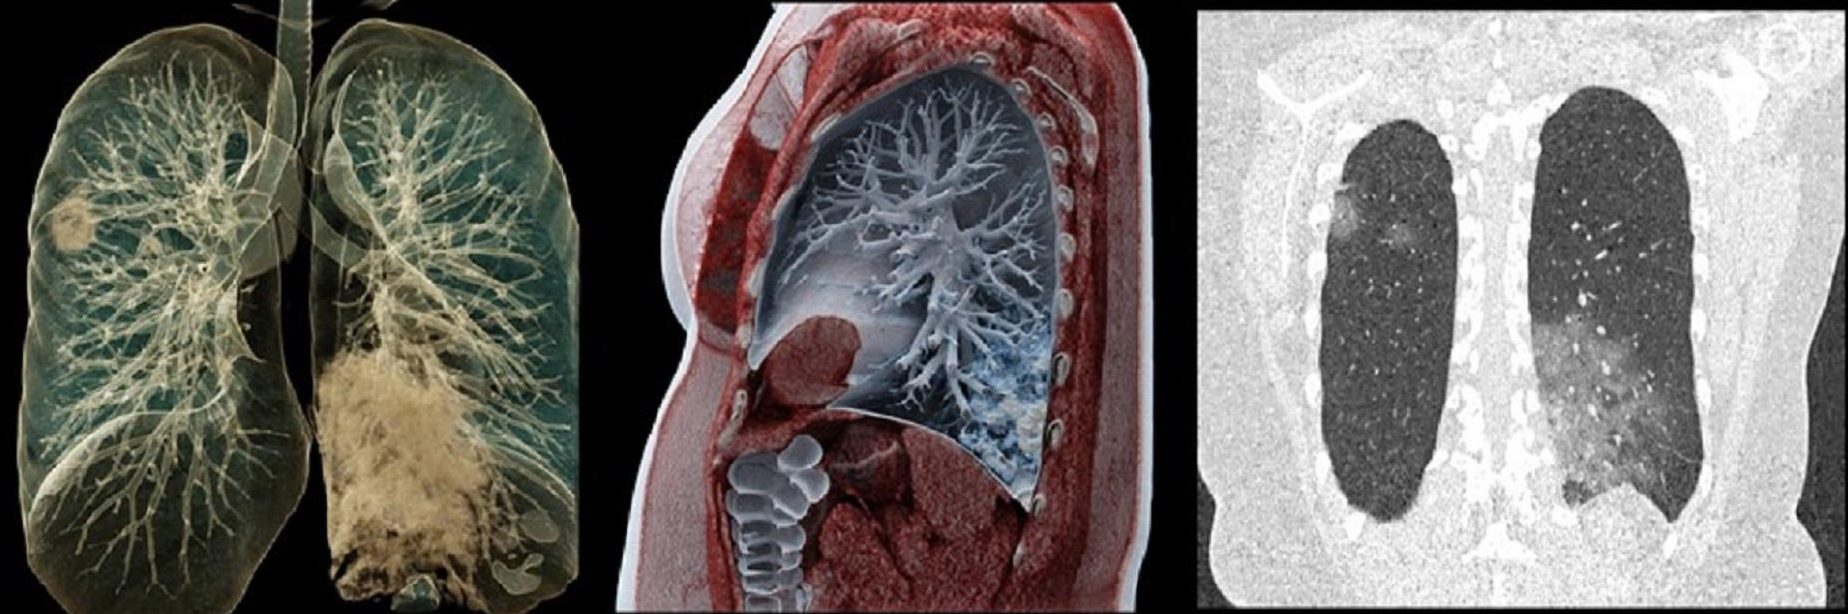

Фотографии и снимки КТ легких без контрастных веществ

Раздел: Визуальный дайджест